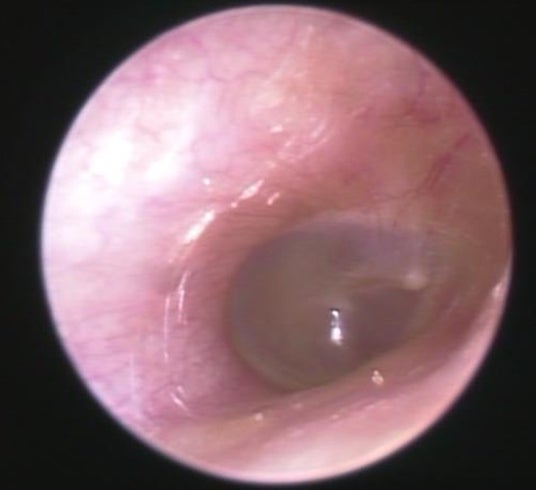

外耳炎:提供そらいろ耳鼻咽喉科センター北駅前院

■外耳炎、耳掃除が主な原因から、イヤホン使用をきっかけに発症するケース増加

昨今、外耳炎や耳カビなども注目される中、今回のラウンドテーブルでは、そらいろ耳鼻咽喉科センター北駅前院 院長の内尾 紀彦先生より、昨今の患者の傾向やイヤホンで起こる外耳炎や耳のトラブルについてお聞きしました。

『外耳炎は、耳の入り口から鼓膜までの「外耳道」と呼ばれる部分の皮膚に細菌が繁殖しておきる病気です。真菌(カビ)が繁殖すると、外耳道真菌症(耳カビ)になります。発症リスクが上がる原因のひとつとして「密閉型イヤホンの長時間使用」が挙げられます。

主な症状は、かゆみ、痛み、耳が詰まったような感じ、聞こえにくさです。特にかゆみは薬で治療しないとサイクルから抜け出せません。温度が20~30度、湿度が60%以上、風通しが悪く日陰だとこのようなカビが繁殖することがあります。密閉型のイヤホンを長時間装着すると、このようなカビができるリスクが高まります。治療法として、外来でカビを掃除して薬を塗ることを繰り返し行いますが、1ヶ月~数ヶ月かかることも稀ではありません。

耳のトラブルを放置すると、治りにくくなる、聴力が低下する、さらに悪化してしまい中耳や内耳、悪性外耳道炎などの重篤な病気が進行してしまう場合もあります。痒みや違和感は無理せずケアをしましょう。』と医師の観点から解説していただきました。